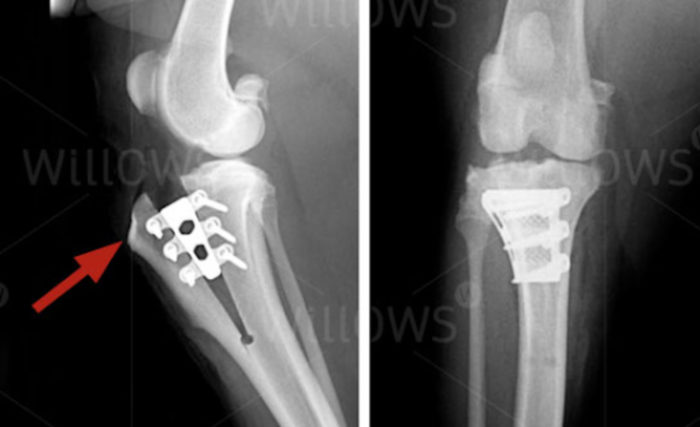

Tibial plateau- leveling osteotomy (TPLO):Is a surgical technique that changes the biomechanics of the stifle joint, eliminating the functional need of the CrCL. This is achieved by making a cut (osteotomy) in the proximal tibia (shin bone) and rotating the plateau to change the tibial plateau angle, thereby eliminating tibial thrust (physiological force that occurs with each step).

Tibial tuberosity advancement (TTA):Is another surgical option to treat CrCL disease that also works by altering the biomechanics of the stifle joint. In this procedure a cut is made in the proximal tibial at the tibial crest (top of the shin bone) and the crest is advanced forward. This technique alters the direction of pull of the quadriceps muscles on the patella (knee cap) tendon. This eliminates tibial thrust when the quadriceps are contracted during weight bearing (providing similar tension to what the cruciate ligament would).

TPLO and TTA surgeries are often recommended for large/ more active breeds with CrCL disease.